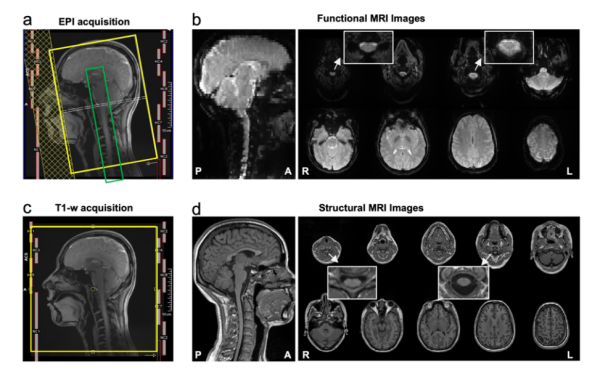

CoSpine成像方案实现了覆盖大脑、脑干、小脑及颈段脊髓的单视野同步采集。这一方案融合多频带并行采集与并行重建算法,可保持1.5毫米高空间分辨率,提升了时间采样效率与图像质量。该策略使皮层-脑干-脊髓神经信号得以在一次扫描中连续获取,为脑–脊髓功能交互研究奠定了方法学基础。

CoSpine功能与结构成像的采集方案及示意图